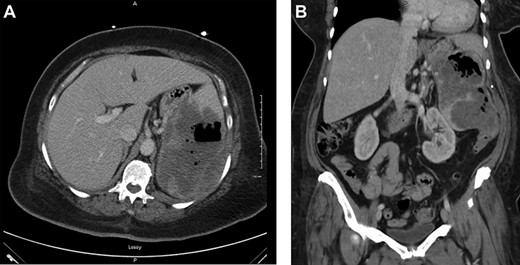

resuscitated with 4 units of packed red blood cell. Upper endoscopy was suspicious for a large paraesophageal hiatal hernia with necrotic mucosa and adherent clot versus penetrating proximal gastric ulcer (Fig. 1) as a possible source of upper gastrointestinal bleeding. Computed tomography showed a largeheterogeneous mass occupying the spleen with air suspicious for splenic abscess versus large mass perforating stomach and colon (Fig. 2). She underwent exploratory laparotomy, en bloc partial gastrectomy with splenectomy and partial left colon resection with colostomy. GSF was observed with the greater curvature of the stomach and a splenocolonic fistula was observed with the splenic flexure of the colon (Fig. 3). There was tumor

(a) Axial view of CT scan with intravenous contrast showed gastrocolic fistula. (b) Coronal view of contrast-enhanced abdominal CT scan. Large splenic mass fistulating into stomach and colon